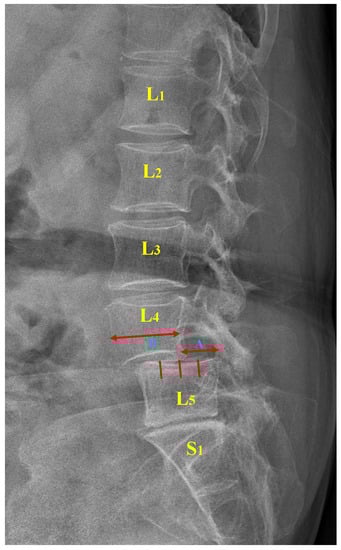

Moreover, the Meyerding classification with five variants is widely used in clinical practice and research owing to its simplicity and ease of application [7,11]. The degree of slippage is classified into five grades by evaluating the extent to which the superior vertebra is displaced relative to the inferior vertebra. Specifically, the ratio of the bare displacement value of the upper vertebra (A) to its width (B) is calculated to obtain a P-grade (as illustrated in Figure 1). Table 1 outlines the relationship between the P-grade and the degree of vertebral slippage. With 50% as the threshold, a P-grade that is either less or more than 50% corresponds to mild or severe slippage, respectively. Of note, a P-grade greater than 100% represents a complete vertebral slippage, the most serious presentation of the condition [12].

Figure 1.

Lumbar spondylolisthesis. L: lumbar vertebra, S: sacral vertebra, A: slip distance between two vertebrae, B: width of the superior vertebra.

The relationship between the bare displacement value A of the lower vertebra and the width B of the upper vertebra is calculated as follows:

The extent of vertebral slippage between the projected point and the upper-right point () of the j-th lumbar vertebra was calculated. The shifted identification algorithm was applied to 394 cases for training, and a threshold value of = 10 was suggested during training. The accuracy, sensitivity, specificity, false-positive rate, and false-negative rate were 88.05% (95% CI, 80%–91%), 89.44% (95% CI, 79%–94%), 84.92% (95% CI, 81%–86%), 7.32% (95% CI, 4%–6%) and 4.63% (95% CI, 4%–15%), respectively (illustrated in Table 3).